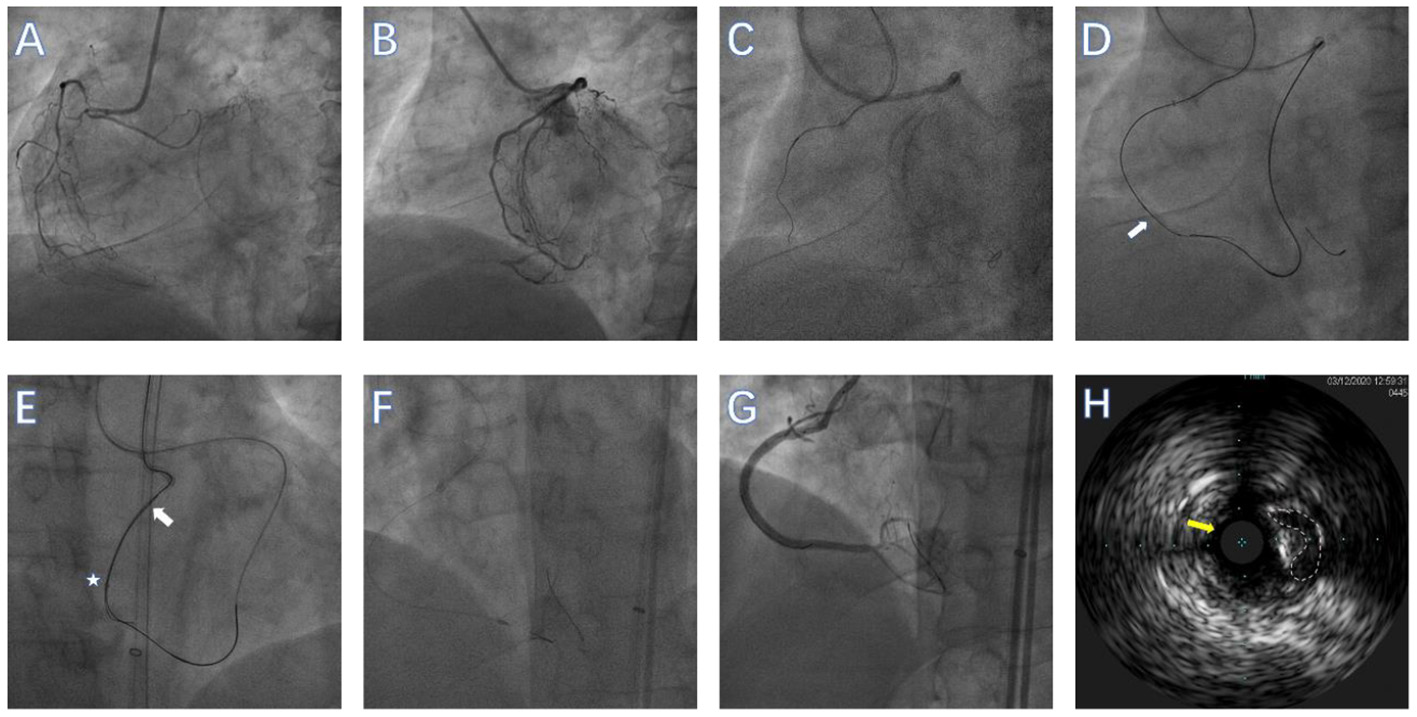

Figure 2

Performing GuidezillaTM reverse controlled antegrade and retrograde subintimal tracking (CART) during rotational atherectomy (RA) in a right coronary artery (RCA) CTO lesion. (A) RCA in left anterior oblique view showing an ambiguous proximal cap without obvious calcification. (B) RCA in left anterior oblique view showing the distal cap of the RCA. (C) Antegrade wire in the subadventitial space of mid-RCA. (D) The CTO lesion was crossed over using the GuidezillaTM reverse CART technique (the white arrow represents the dilated balloon). (E) Retrograde wire (white arrow) was advanced into the GuidezillaTM (white star) of the RCA and externalized. (F) Rotational atherectomy was then performed using a 1.25-mm burr. (G) Angiography after successful CTO-PCI. (H) Intravascular ultrasound confirmed that the guidewire (yellow arrow) was in the subadventitial space (The white dotted line represents the true lumen of the vessel).